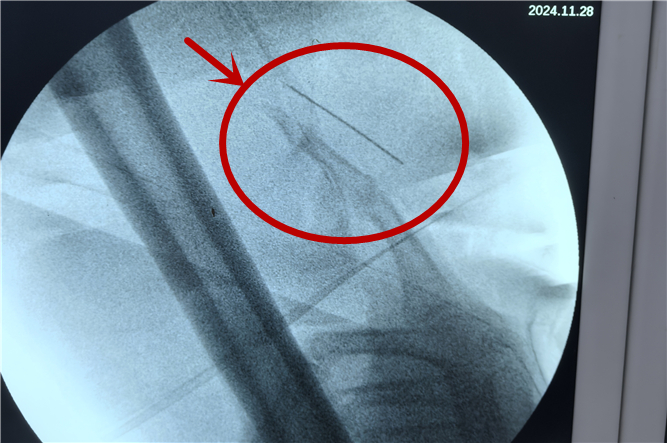

手術(shù)前的最后一次拍片顯示,“縫衣針”位于大腿中段大收肌內(nèi),針尖位于股深動(dòng)脈處,針尾在坐骨神經(jīng)處。手術(shù)時(shí)可見右大腿近端內(nèi)后側(cè)約1毫米針孔,周圍皮膚充血。手術(shù)中,發(fā)現(xiàn)異物在肌肉內(nèi)移動(dòng)幅度大,尋找困難,克氏針橫堅(jiān)C臂定位照相不宜定位!

為避免鋼針損傷血管神經(jīng),必須盡快取出。最后醫(yī)生用手指在肌肉間逐步探查照相確定異物位置,終于在探查定位40余次后順利取出。

李長青主任帶領(lǐng)團(tuán)隊(duì),憑借一份“咬定青山不放松”的執(zhí)著、一腔“千磨萬擊還堅(jiān)勁”的熱情,30分鐘后將縫衣針完整取出。